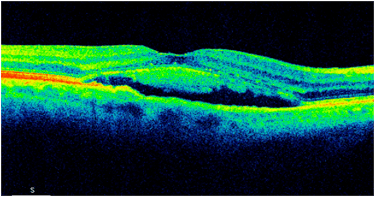

1. SOCT. Jest zwykle pierwszym badaniem wykonywanym u pacjenta z podejrzeniem CSCR. W postaciach prostych, ostrych najczęstszym objawem jest obecność hiporefleksyjnej przestrzeni płynowej pod siatkówką sensoryczną oraz wydłużenie fotoreceptorów. Dodatkowo obecne jest zwiększenie grubości siatkówki sensorycznej – obrzęk. Przy postaciach skomplikowanych mogą być obecne także ogniska PED. W miarę trwania CSCR wydłużenie fotoreceptorów zmniejsza się i zostaje zastąpione przez ziarnistości odpowiadające skupiskom makrofagów. W niektórych sytuacjach SRF może zawierać hiperrefleksyjne ogniska odpowiadające fibrynie (taki obraz jest charakterystyczny dla CSCR w trzecim trymestrze ciąży). Postaci długotrwałe CSCR zwykle wykazują bogactwo objawów widocznych w SOCT. Charakterystyczne jest ścieńczenie siatkówki sensorycznej, niekiedy cystowate zmiany w siatkówce sensorycznej, ubytki w RPE oraz ogniska PED.

Obraz SOCT w różnych postaciach CSCR. Postać ostra charakteryzuje się wydłużeniem fotoreceptorów oraz brakiem ścieńczenia siatkówki sensorycznej. Z kolei postaci przewlekłe mogą przybierać różne formy morfologiczne: na jednym zdjęciu widoczna jest hiperrefleksyjna fibryna w płynie siatkówkowym oraz ziarnistości na granicy siatkówki sensorycznej. Z kolei drugi przykład pokazuje znaczne ubytki siatkówki sensorycznej pomimo resorpcji SRF po wykonanej SML.